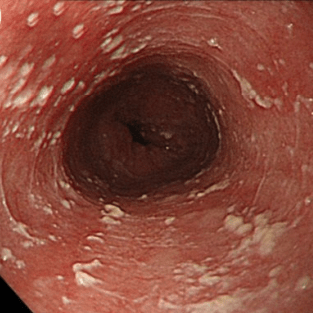

Эндоскопические признаки кандидоза пищевода — гиперемия и контактная ранимость слизистой оболочки, а также фибринозные налеты различной локализации, конфигурации и размеров. Среди всего разнообразия визуальных признаков кандидоза пищевода можно выделить три группы типичных изменений:

Катаральный эзофагит. Наблюдают диффузную гиперемию различной степени (от слабовыраженной до яркой) и умеренный отек слизистой оболочки. Характерным эндоскопическим признаком является контактная кровоточивость слизистой оболочки, иногда — с образованием нежного, белесоватого («паутинообразного») налета на слизистой оболочке. Эрозивных изменений не отмечают.

Фибринозный (псевдомембранозный) эзофагит. Наблюдают бело-серые или бело-желтые рыхлые налеты в виде округлых бляшек диаметром от 1 до 5 мм, выступающие над ярко гиперемированной и отечной слизистой оболочкой. Контактная ранимость и гиперемия слизистой оболочки заметно выражены.

- Катаральный эзофагит. Характеризуется гиперемией слизистой пищевода и умеренной отечностью. На кандидозную инфекцию указывает тонкий паутинообразный налет на эпителии, контактная кровоточивость.

- Фибринозный эзофагит. В пищеводе образуются беловато-серые налеты в виде бляшек размером до 0,5 см. Гиперемия, отечность и кровоточивость слизистой оболочки выражены интенсивнее, чем при катаральной форме.

- · Диагноз кандидозного эзофагита устанавливается, как правило, при эзофагоскопии, когда выявляются белые и белесовато-желтые бляшки и бляшкоподобные налеты на слизистой оболочке пищевода. Зачастую участки белесоватого налета носят диффузный характер, и покрывают всю поверхность слизистой оболочки пищевода.

- · Патогномоничным признаком кандидозного эзофагита является тот факт, что налет с трудом снимается биопсийными щипцами и после его удаления остаются участки осаднения слизистой оболочки.

Степень I: Несколько приподнятых белесоватых бляшек размерами до 2 мм в диаметре, с гиперемией, но без отека или язв.

Степень II: Множественные приподнятые белесоватые бляшки размерами более чем 2 мм в диаметре с гиперемией вокруг, но без отека или язв

Степень III: Сливные линейные и узловатые приподнятые бляшки, с гиперемией и язвами

Степень IV: Те же изменения, что и при III степени, плюс контактная кровоточивость слизистой оболочки и иногда сужение просвета пищевода